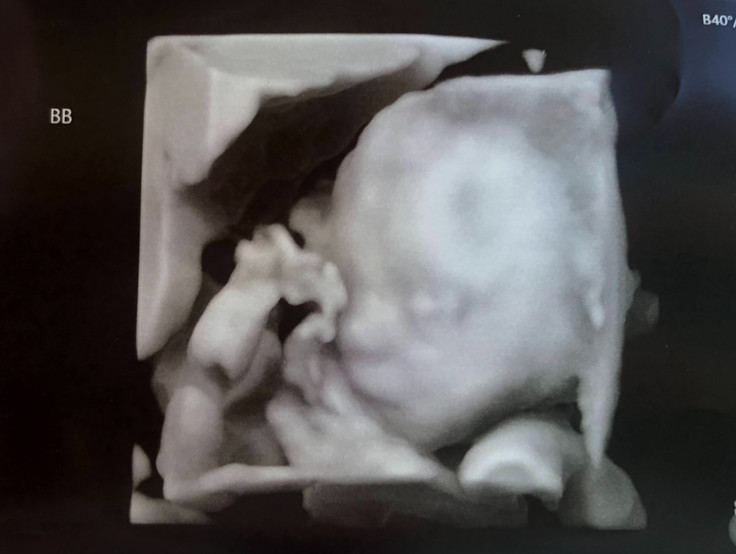

Our second ultrasound was at 9 weeks. This would be my last ultrasound before 'graduating' from the fertility clinic back to my normal OB. I remember laying on the table trying to make sense of what I was seeing on the screen when the doctor said, "Well that's interesting. Was there just one baby last time?" Corey and I responded that of course there was only one baby last time, we only had one embryo transferred. Then the doctor dropped a bombshell, "Well there are two now." Since we only had one embryo transferred and there was only one baby at the first ultrasound (or so we thought), the thought of twins was so far from our mind at this point, to say we were shocked is an understatement.

Through our shock, the doctor explained I was pregnant with identical twins, the only type of twins that can get missed on an early ultrasound (like they were at our first one) because the babies are so tiny and close together this early in a pregnancy. He explained there are three types of identical twins, all defined by the number of, and separation of, placenta and amniotic sacs. We are expecting monochorionic diamniotic (MoDi) identical twins. This means our twins share one placenta but each have their own amniotic sac. All twins are considered high risk, but MoDi twins are considered the second highest risk of the four types of twins (fraternal and three types of identical). Twins that share an amniotic sac and placenta (monochorionic monoamniotic or MoMo) are the highest risk. We were sent home with this bombshell and instructions to schedule an appointment ASAP with my normal OB.